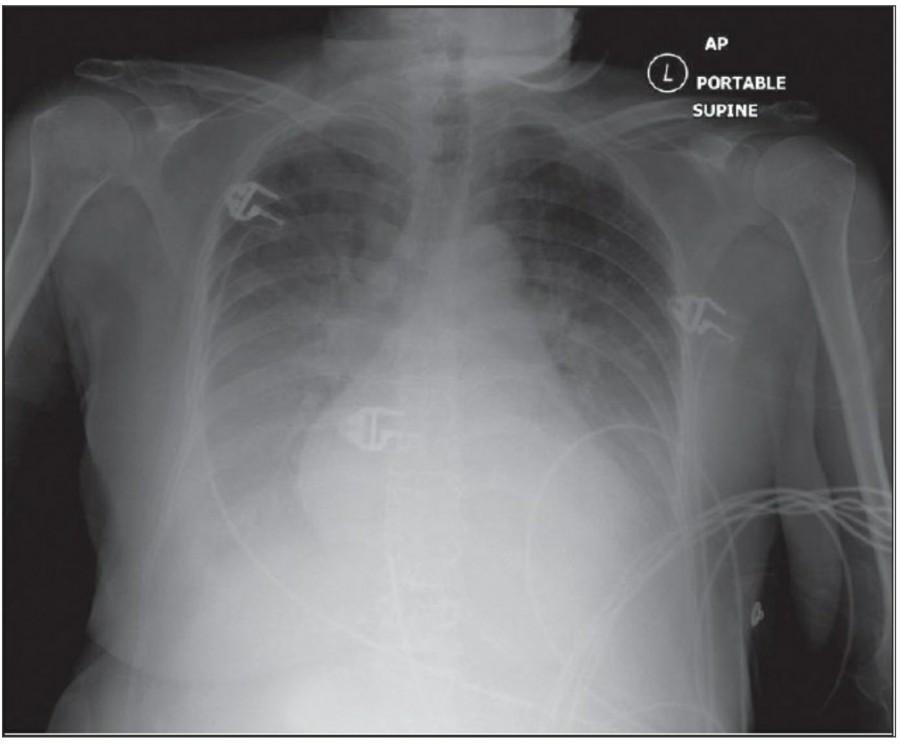

중환자에서 pneumothorax의 진단은 종종 supine radiograph에서 내릴 수 있다. Supine position에서 공기는 anteromedial 방향으로 모이게 되는데, apical air collection이 있을 경우 large pneumothorax가 있음을 시사한다. 공기는 lung과 diaphragm 사이의 subpulmonic location에 trap 되어 있을 수도 있다. 공기가 costophrenic sulcus로 anterolateral extension 될 경우, 이 costophrenic sulcus의 radiolucency를 증가시키는데, 이를 deep sulcus sign이라고 한다. Subpulmonic pneumothorax의 다른 특징으로 diaphragm의 superior surface와 IVC 윗부분이 뚜렷하게 보일 수 있다.

중환자에서 tension pneumothorax의 진단은 매우 힘들다. ARDS와 같은 lung의 병리적인 기전이 lung compliance를 감소시킴으로써 total lumg collapse를 막는다. 또한 tension pneumothorax의 특징인 mediastinal shift가 PEEP으로 인해 나타나지 않을 수 있다. Chest X ray 상에서 tension pneumothorax는 hemidiaphragm의 depression이나 heart border, SVC, IVC의 이동으로 나타날 수 있다.